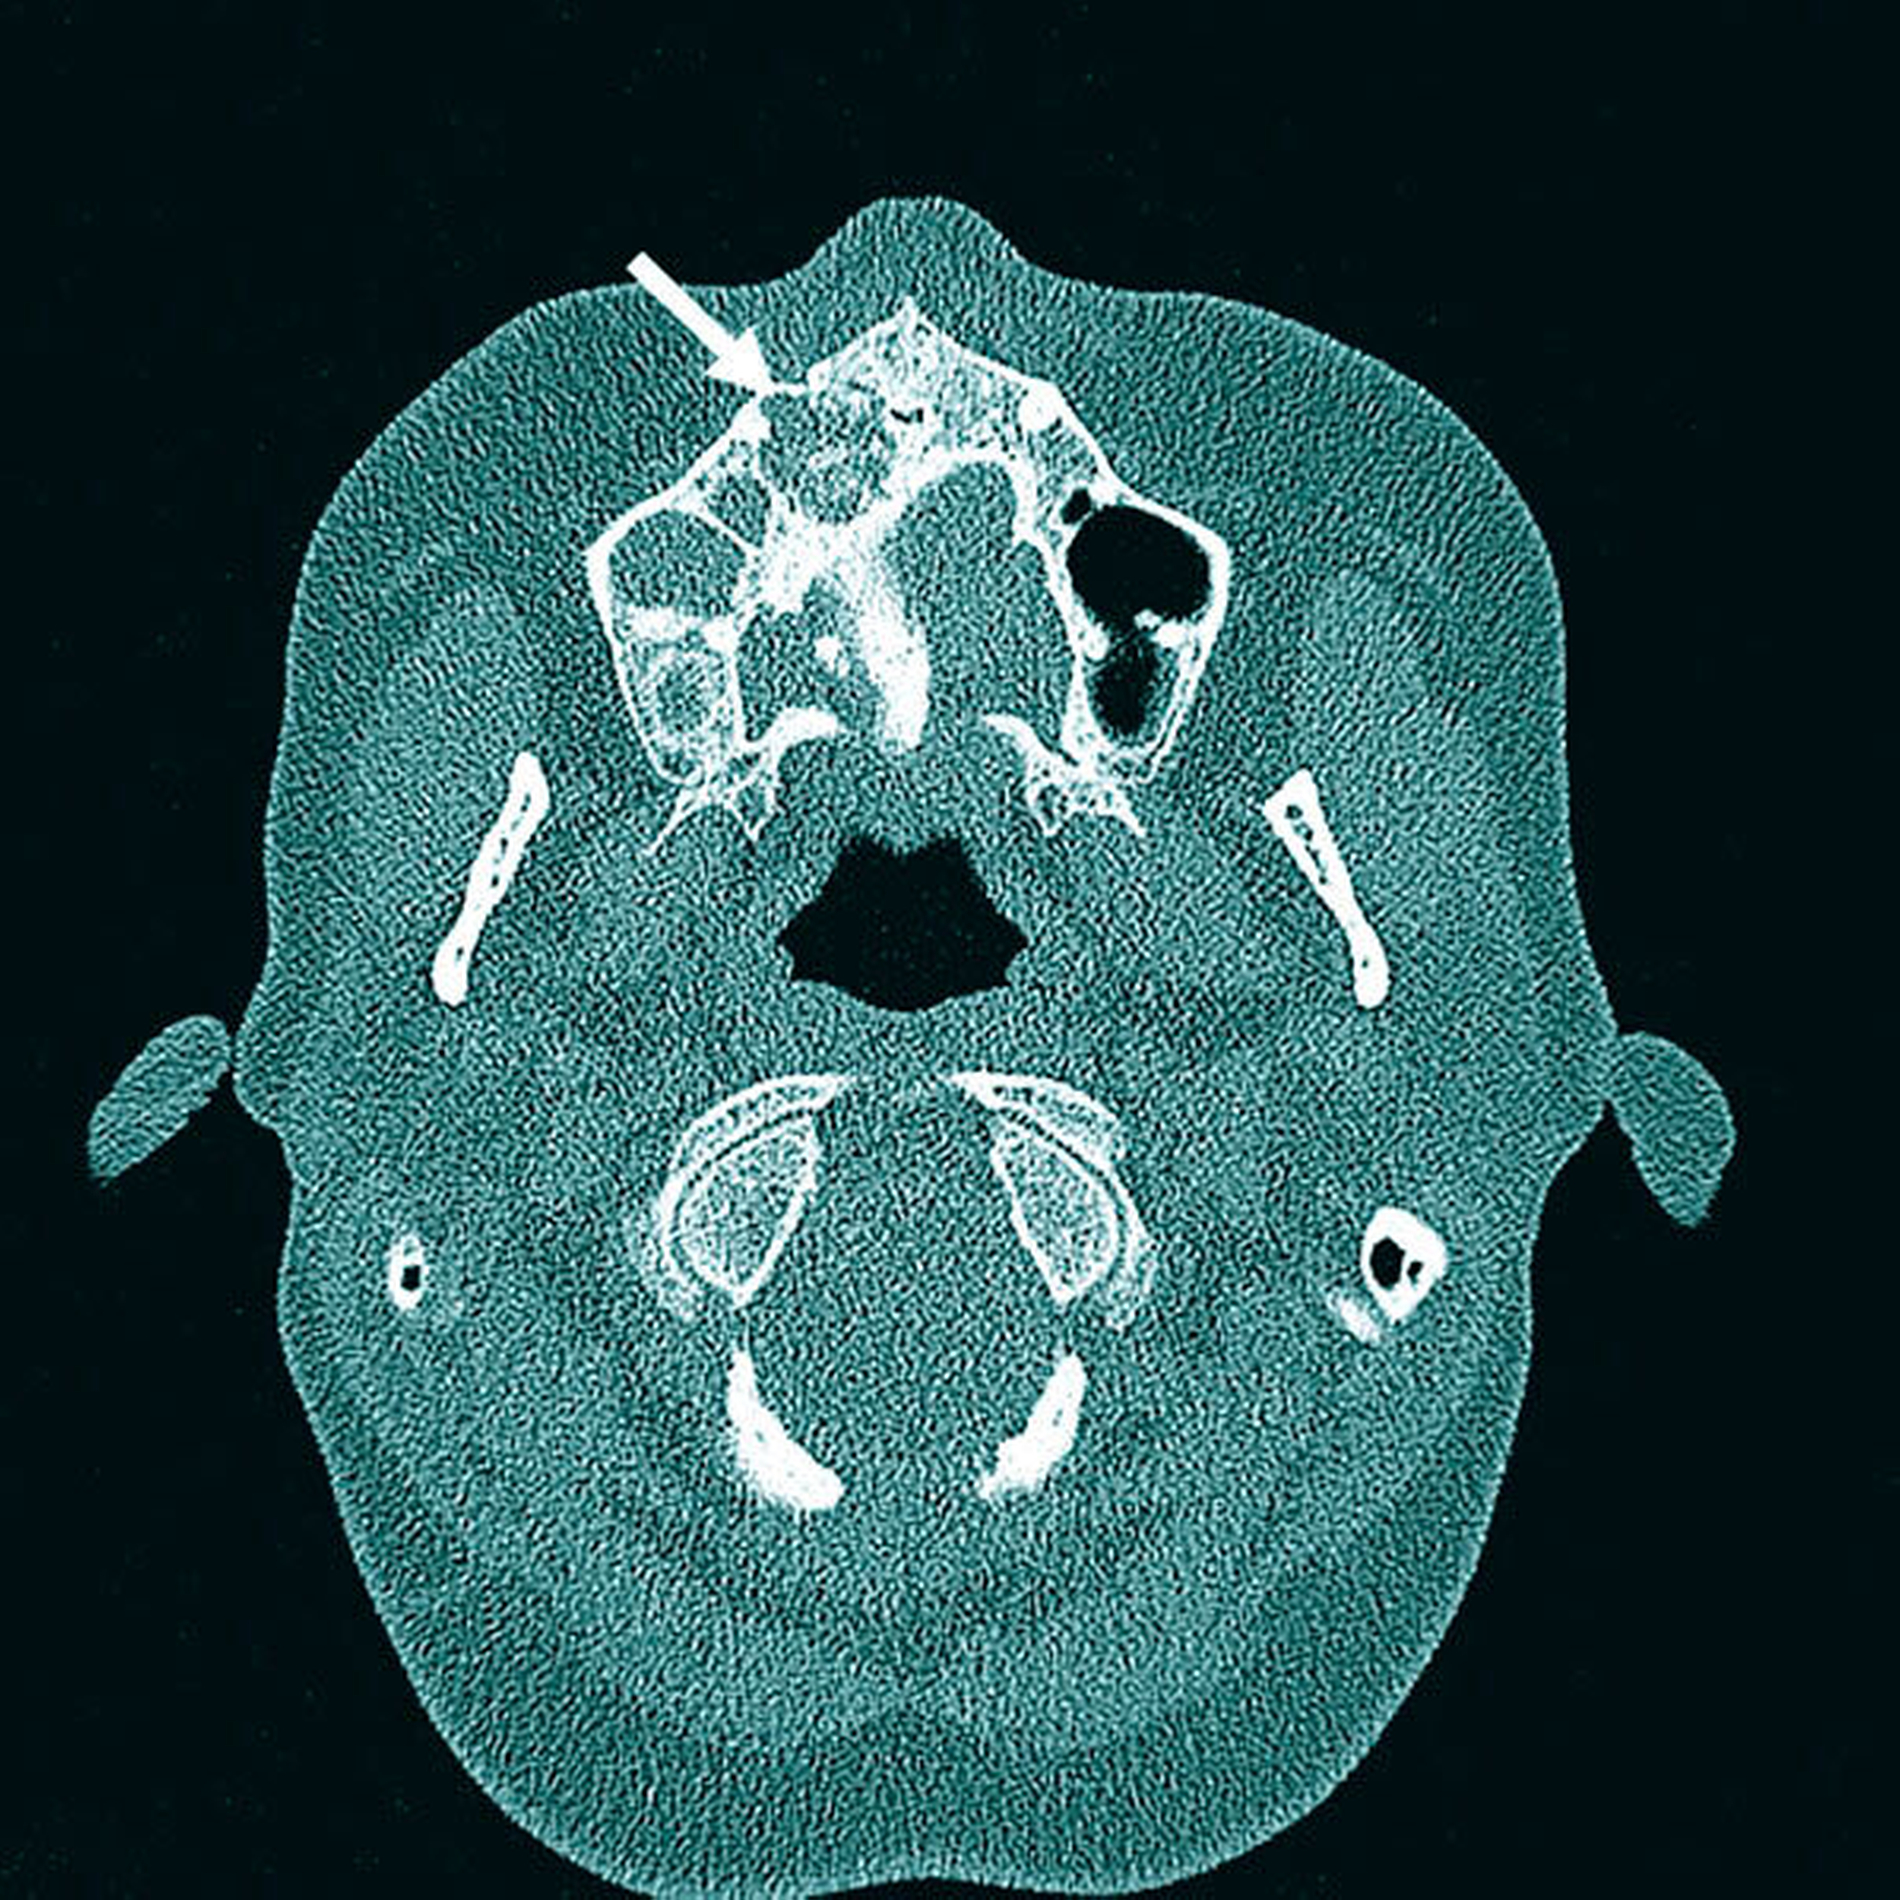

In der Diagnostik kommt demnach neben der eingehenden oralen Inspektion der bildgebenden Untersuchung eine zentrale Bedeutung zu. Hierbei ist zu beachten, dass eine klassische konventionelle Panoramaschichtaufnahme als unzureichend gilt und – gerade auch im Sinne einer präoperativen Diagnostik – durch geeignete 3-D-Verfahren zu komplettieren ist. Außerdem wird empfohlen, eine histopathologische Aufarbeitung des Gewebes durchführen zu lassen, um zum einen maligne Prozesse ausschließen zu können und zum anderen die Diagnose zu sichern.